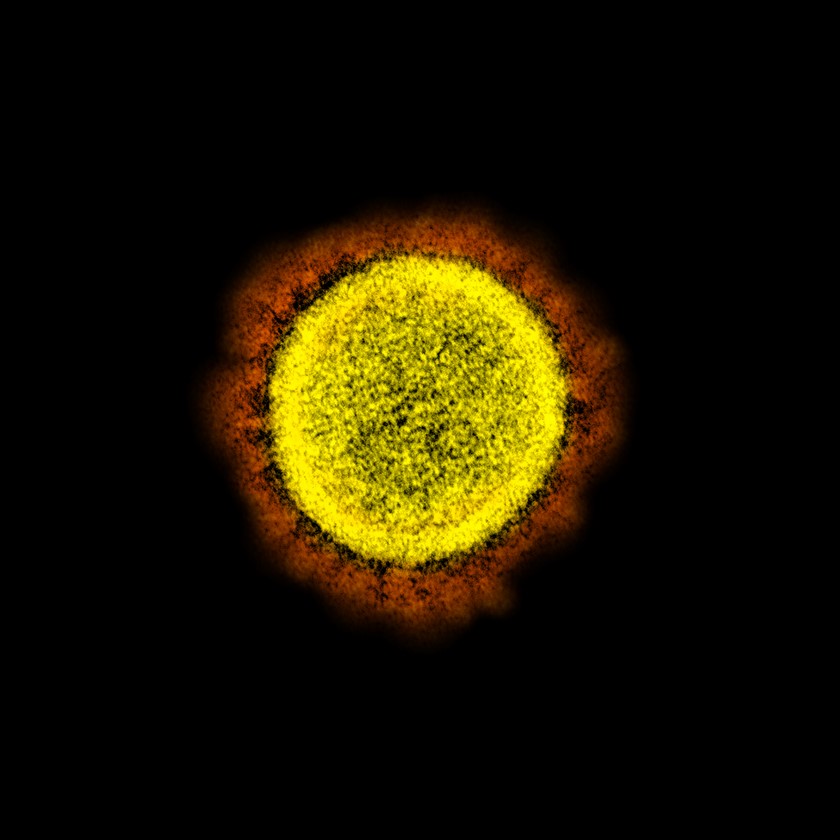

Durante las últimas semanas las noticias se han centrado en el Coronavirus Covid-19, el cual tiene a millones de personas en cuarentena para evitar su propagación, aunque seguramente todavía no le has puesto una cara al patógeno responsable de todo esto, por fortuna el Instituto Nacional de Alergia y Enfermedades Infecciosas de Estados Unidos (NIAID) ha compartido varias imágenes tomadas con un microscopio electrónico de este virus.

Dichas imágenes han sido coloreadas artificialmente para mostrar más detalladamente cómo el patógeno ataca las células humanas, estas células que fueron extraídas de pacientes enfermos con Coronavirus para su investigación en Fort Detrick, Maryland.

Este virus mide entre 120 y 160 nanómetros de diámetro, por lo que solo puede ser observado a través de un microscopio electrónico y como puede evidenciarse en las imágenes el patógeno se adhiere a la membrana celular gracias a un recubrimiento de una capa de lípidos con espinas de proteínas, las cuales se asemejan a una corona, de allí su nombre.

Al estar adherida usa a la célula para crear más copias de sí misma hasta que la célula infectada implosiona, liberando más virus para infectar a otras células, dañando el tejido pulmonar y causando la sintomatología propia de esta enfermedad.